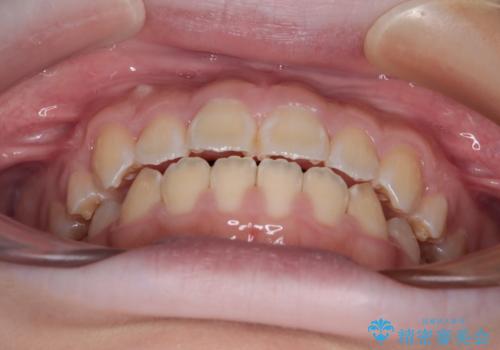

- 前歯が開いて飛び出していることを気にして来院された患者様です。

舌の突出癖により上下前歯は接触できず、更には前方に押し出されて出っ歯になっている状態でした。

上下左右の第一小臼歯4本を抜歯し、ワイヤー装置での抜歯矯正を行っていくのですが、原因である舌の突出癖を改善しないことには治療がうまく進められないため、舌のトレーニングを徹底するよう指導していくこととしました。